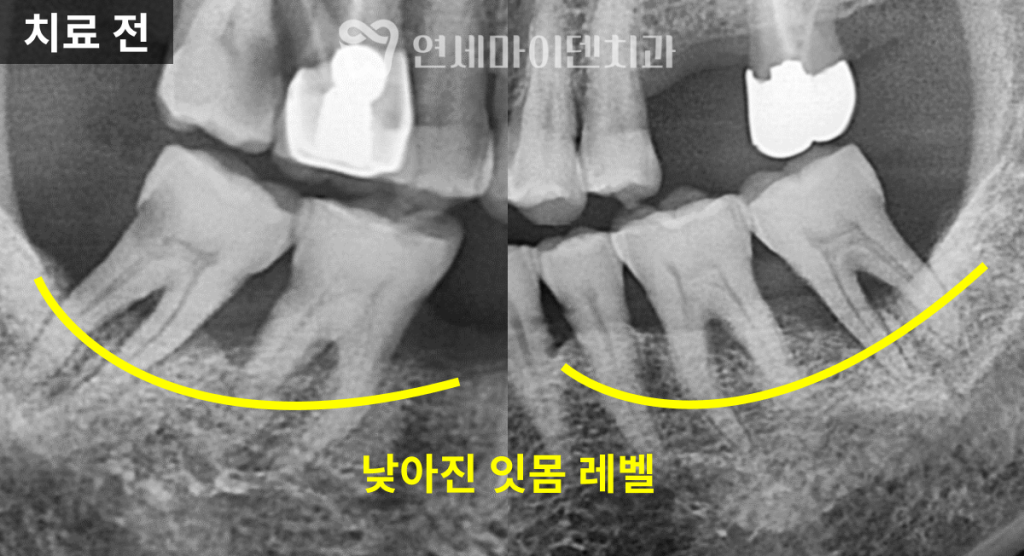

70대 고령 환자의 건강보험 임플란트 케이스입니다.70대 고령 환자 임플란트 진단

이번 케이스는 70대 환자분으로,

어금니 두 개에 임플란트 치료가

필요한 상황이었습니다.하지만 임플란트 치료는

결손 부위만 보고 바로 수술을 결정해서는 안 됩니다.어금니와 앞니 주변의 잇몸 상태,

충치 유무,

그리고 전체적인 교합 관계는

임플란트의 장기적인 안정성과

직결되기 때문입니다.

이번 사례에서도

임플란트가 필요한 부위 외에

다른 치아에서

잇몸 질환과 충치가 함께 발견되었습니다.따라서 이번 치료는

오랫동안 건강하게 유지될 수 있습니다.3D 가이드 임플란트 계획

임플란트는

뼈와 잇몸의 상태를 고려해

정밀하게 설계되어야 하는 치료입니다.

수술 전 3D CT 촬영을 통해

임플란트 식립 위치와 각도를

미리 계획했고,

주변 해부학적 구조물을 피하면서

안정적인 식립이 가능하도록 준비했습니다.

또한 염증 발생 가능성을 낮추기 위해

이번 케이스에서도

임플란트 픽스처를

뼈 레벨보다 약간 안쪽으로 식립해

안정성을 높였습니다.건강보험 임플란트 최종 보철

치료가 끝난 이후에도

6년 이상 장기 추적 관찰을 진행했습니다.치료를 받지 않았던 일부 치아는

시간이 지나면서

추가 임플란트가 필요하게 되었지만,초기에 임플란트를 식립한 부위와

앞니 레진 수복 부위는

큰 문제 없이

안정적으로 유지되고 있었습니다.건강보험 임플란트 제도는